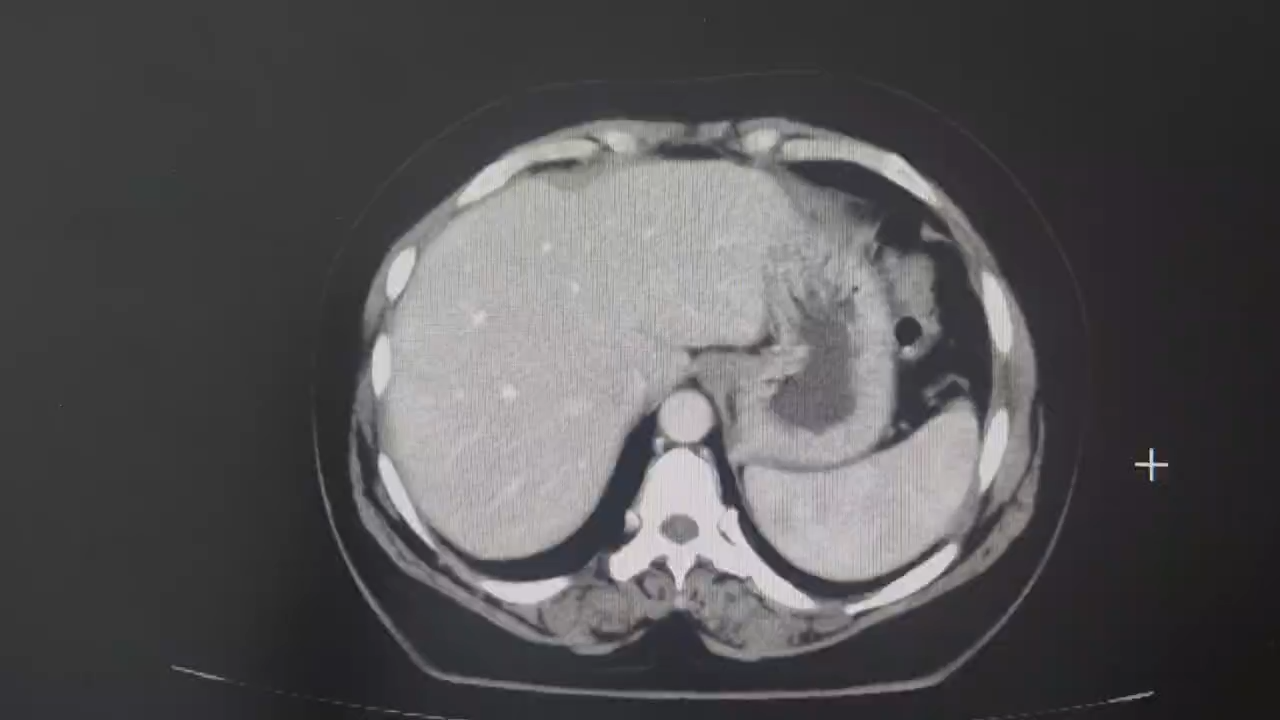

腹部增强CT检查:

动脉期:

术前讨论:科室集体讨论后认为患者腹腔内肿物来源于卵巢的可能性较大,但也不排除其他来源,尤其是肠系膜来源,从腹部增强CT来看,患者腹腔内肿物供血动脉来源于肠系膜上动脉根部,即空肠第二支,空肠第一分支动脉位于肿瘤上极左侧,受压偏移明显,肠系膜上动脉及上静脉主干均明显受压变形。从CT上来看,肿瘤内没有明显强化表现,像囊性肿瘤。部分医生认为可以选择腔镜手术,先进行减压后再切除,但是考虑到这么大的肿瘤,万一是恶性的,先穿刺减压就违反了无瘤原则。最后决定备血后进行开放手术治疗。